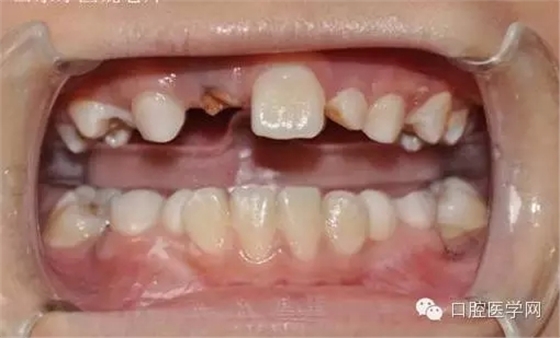

基本資料:男8歲、祖籍山東滕州、二年級。

主訴:門牙遲遲不長

現病史:右乳上一牙根滯留。

埋伏牙在臨床較常見,可能于頜骨退化有關,現以一例典型埋伏牙為例,講述簡簡單單牽引全過程,及注意事項。

小兒8歲發(fā)現右上門牙遲萌,右乳一殘根。